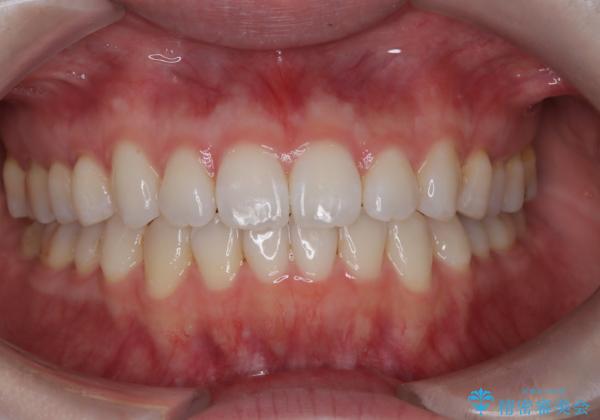

【インビザライン】がたつきをなおしたい

- 上下の前歯の凸凹が気になり、来院されました。

インビザラインで綺麗に仕上がり、満足していただきました。